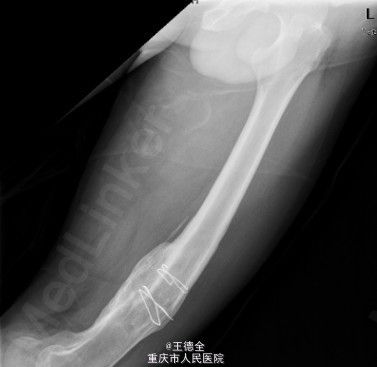

患者男,40岁,因“左股骨下段骨折术后4+年,左膝反复肿痛2年余”入院;自诉于4年前不慎被石块砸伤左大腿,伤后即觉左大腿疼痛,流血,左下肢活动障碍,患者伤后即到当地医院就诊,诊断为:"左股骨下段开放性骨折",予骨折切开复位内固定术,术后3个月下地行走,术后内固定螺钉松动、脱落,近两年来出现左膝关节肿胀、疼痛,活动时肿胀、疼痛症状加重,无畏寒发热、肢端麻木等,患者病后曾到当地医院就诊,予服药治疗后症状无明显好转,为进一步诊治遂来我院就诊,门诊拟"左膝骨性关节炎"收住我科,病程中,患者一般情况尚可,睡眠、饮食可,大小便正常,体重无明显改变。

查体:生命体征平稳,心肺腹未见异常;膝关节周围课件明显肿大,左膝关节活动受限,皮温略高;左股骨下端可扪及肿大,腘窝有一处大小约5x4cm的肿块,辅查x线片如下。